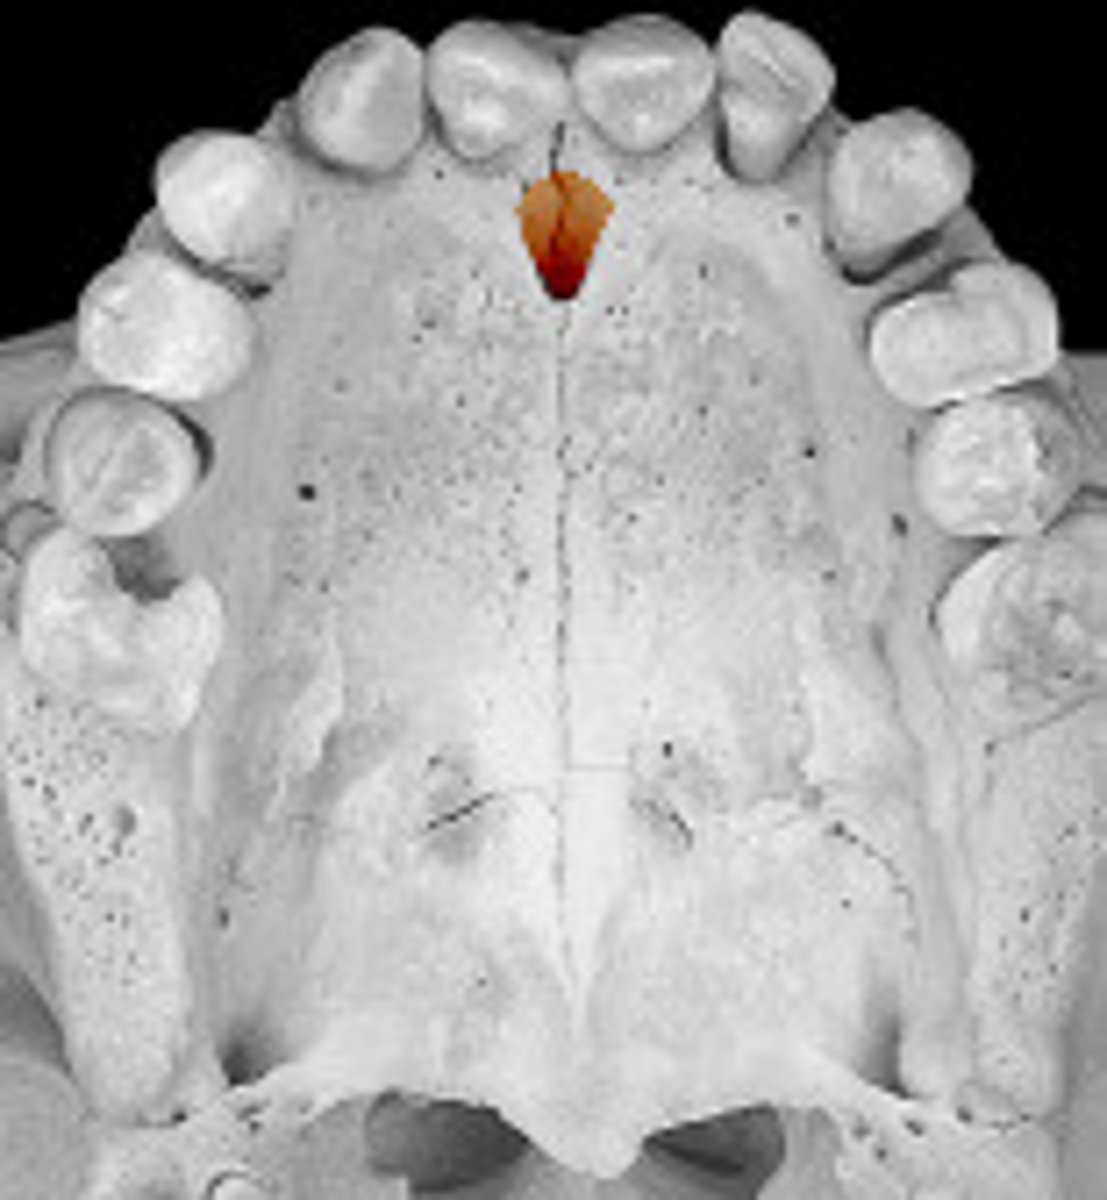

median suture

"crack" between roots of maxillary central incisors

area of incomplete fusion

radiolucent

incisive foramen

hole in the bone of the maxilla and between roots of incisors